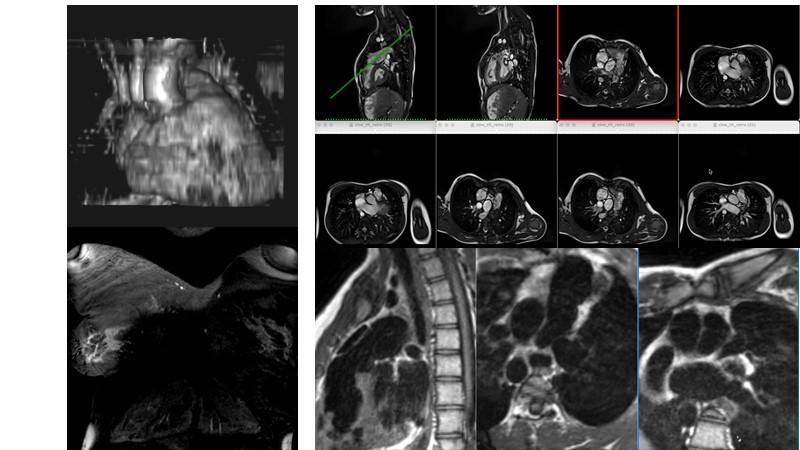

The right valves for the right ventricle: Venus MedTech tricuspid and pulmonary replacement systems

In this session from PCR London Valves 2022, discover the new Venus MedTech technology for tricuspid and pulmonary valve replacement, and a review of the clinical indications, selection criteria and procedural details.

- To learn about Venus MedTech technology, clinical indications and procedural details of valve replacement systems

- To learn more about the clinical experience and outcomes with Cardiovalve tricuspid and Venus P-valve

- To have the tools to select the best candidates for treatment